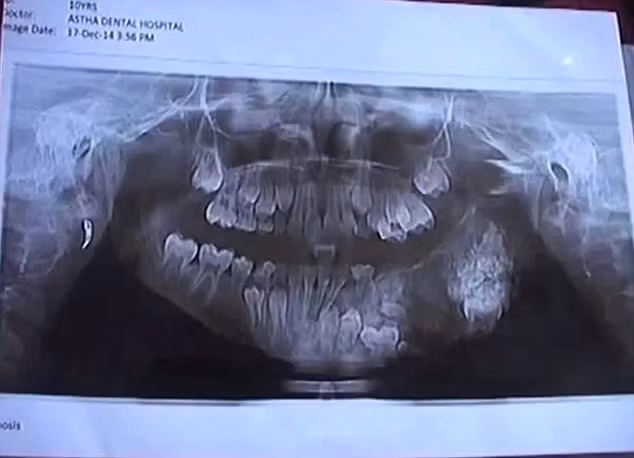

| Ảnh chụp X-quang cho thấy 80 chiếc răng mọc ra từ hàm của cậu bé 7 tuổi ở Ấn Độ. |